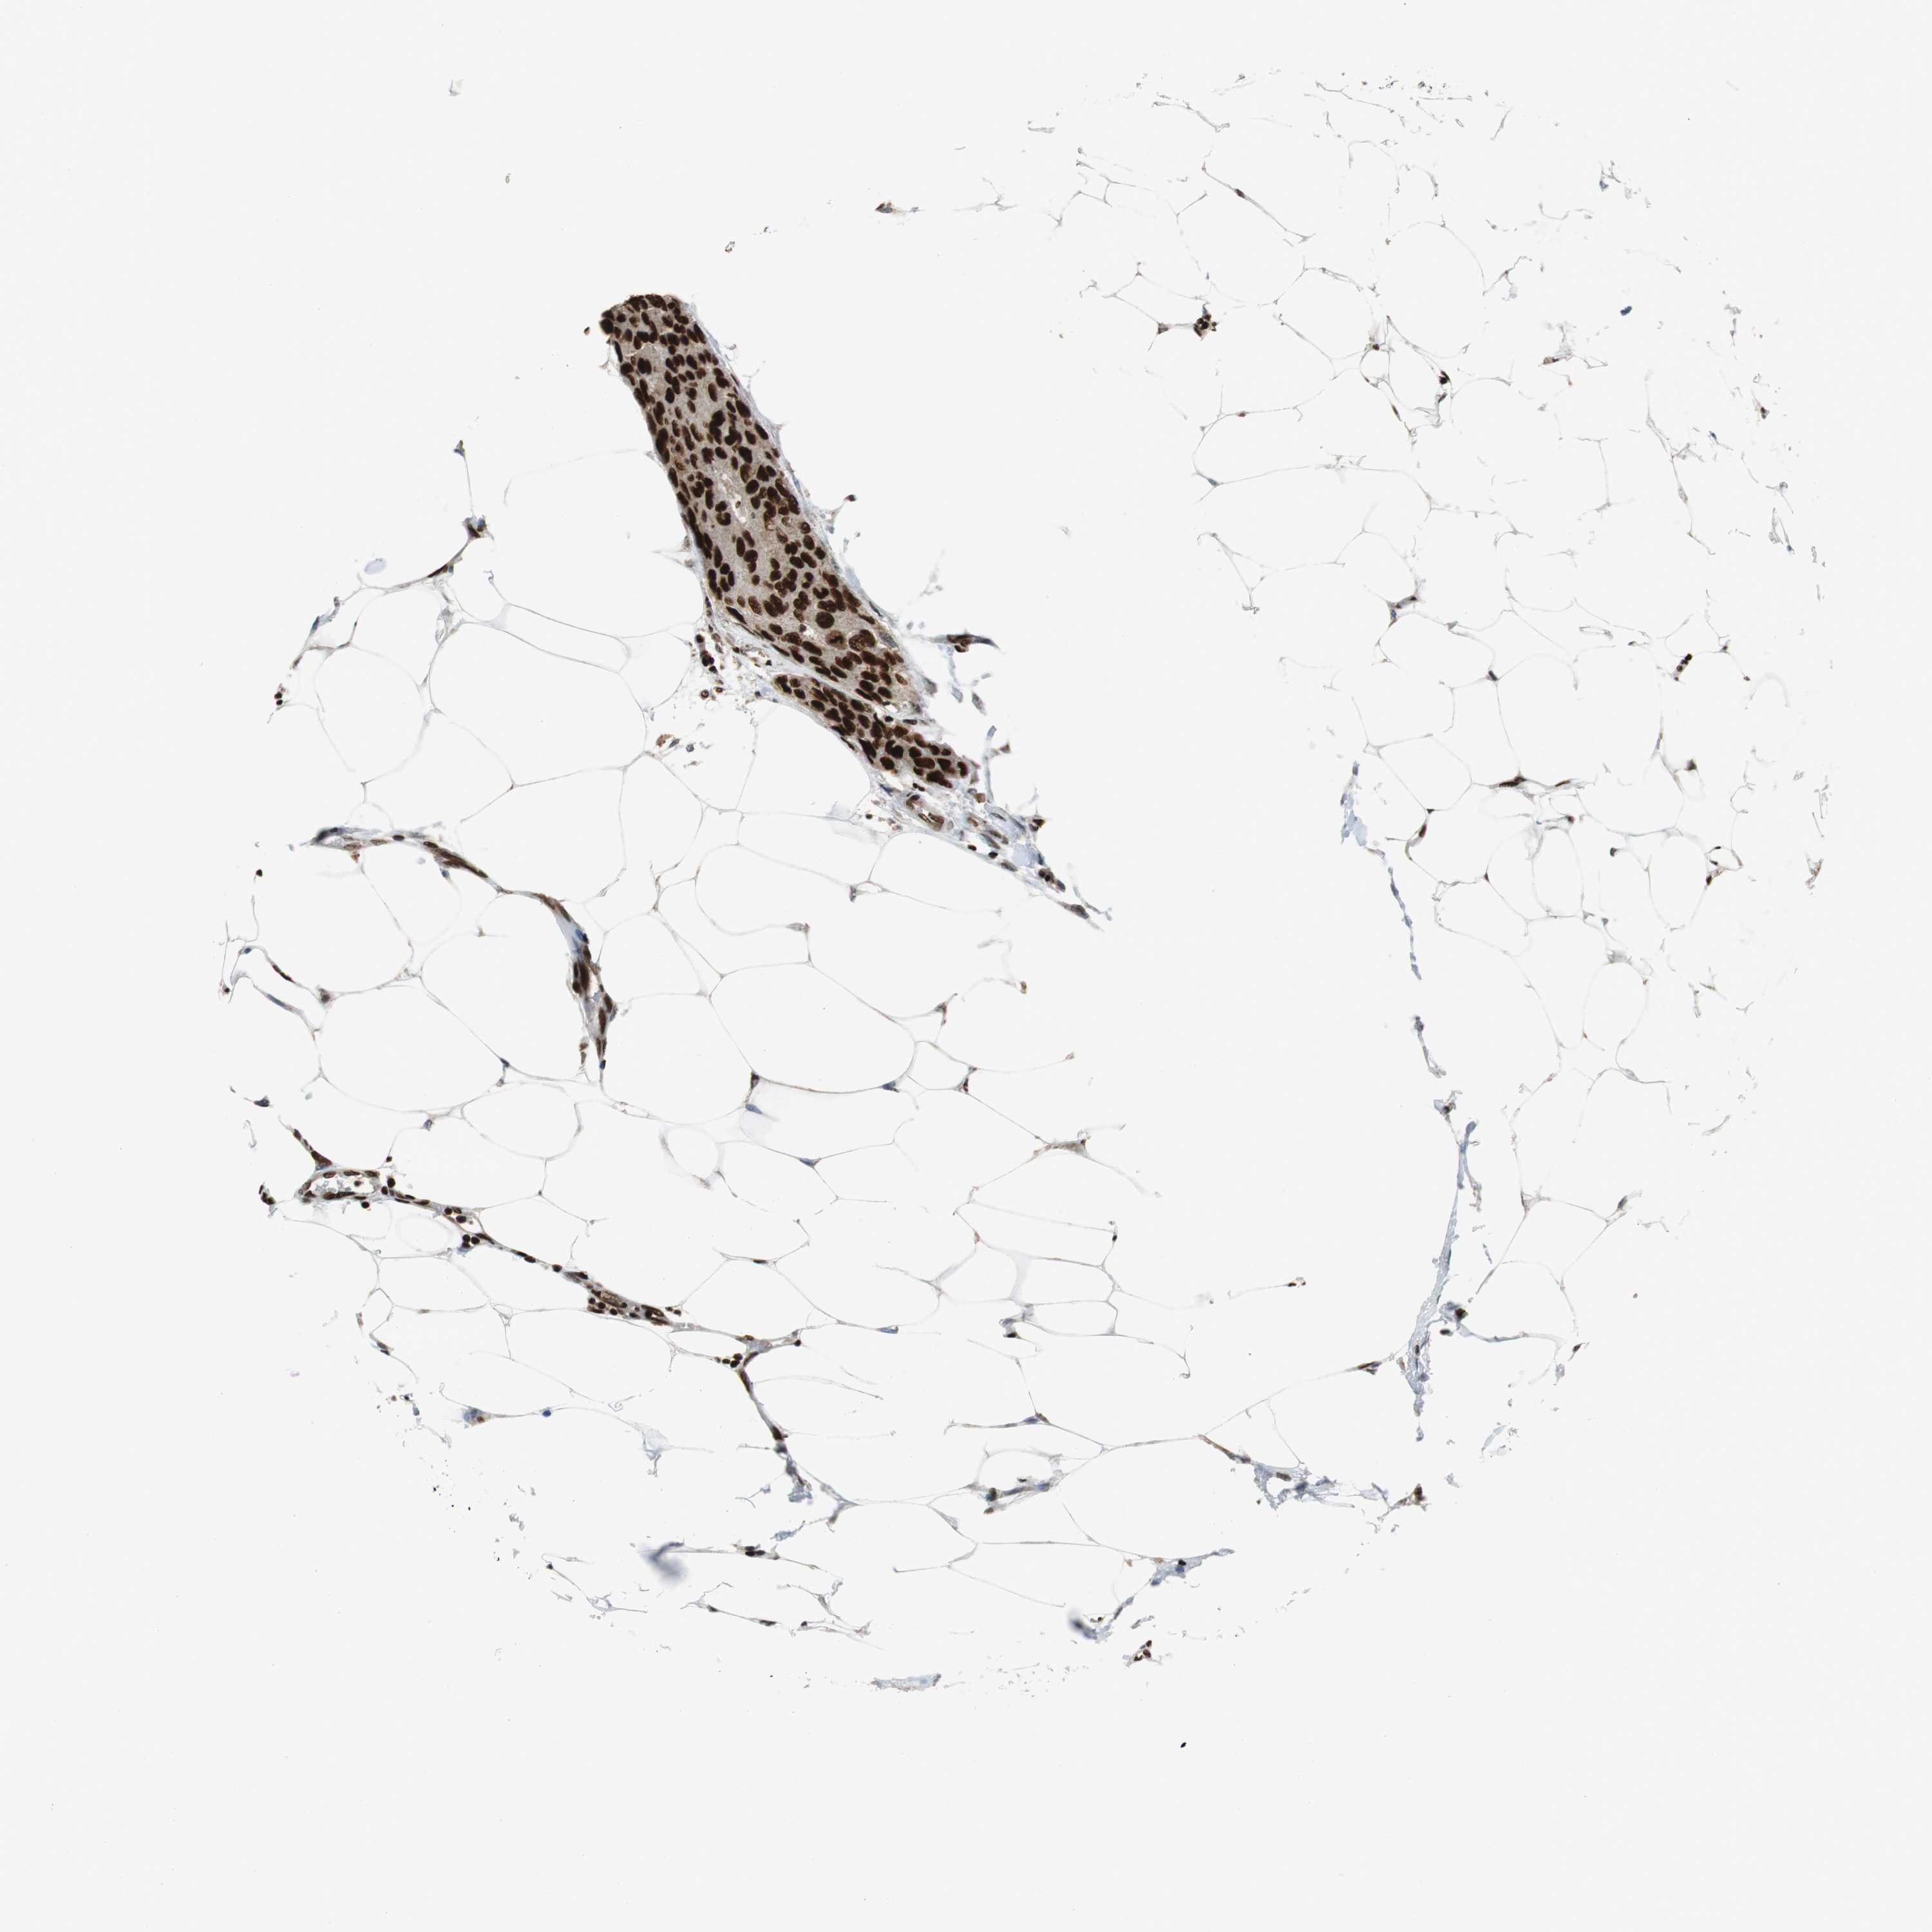

BRCA TCGA BRCA VALIDATION PROTEIN EXPRESSION

ANTIBODIES

AND

VALIDATION